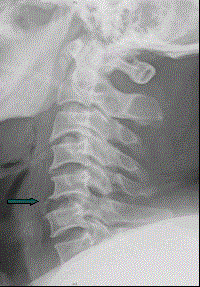

患者男,38岁,车祸伤后导致颈部疼痛、四肢瘫痪,排尿、粪失禁,ASIA分级C级,入院时间为伤后6 h,佩戴颈托入院。于急诊行颈椎正侧位X线片(如图)。...

问题 患者男,38岁,车祸伤后导致颈部疼痛、四肢瘫痪,排尿、粪失禁,ASIA分级C级,入院时间为伤后6 h,佩戴颈托入院。于急诊行颈椎正侧位X线片(如图)。 此患者入院后为挽救脊髓功能,最需要的治疗是

选项 A、甘露醇静脉滴注 B、抗休克治疗 C、GM1神经营养治疗 D、呋塞米静脉滴注 E、大剂量MP冲击治疗

答案 E

解析 E